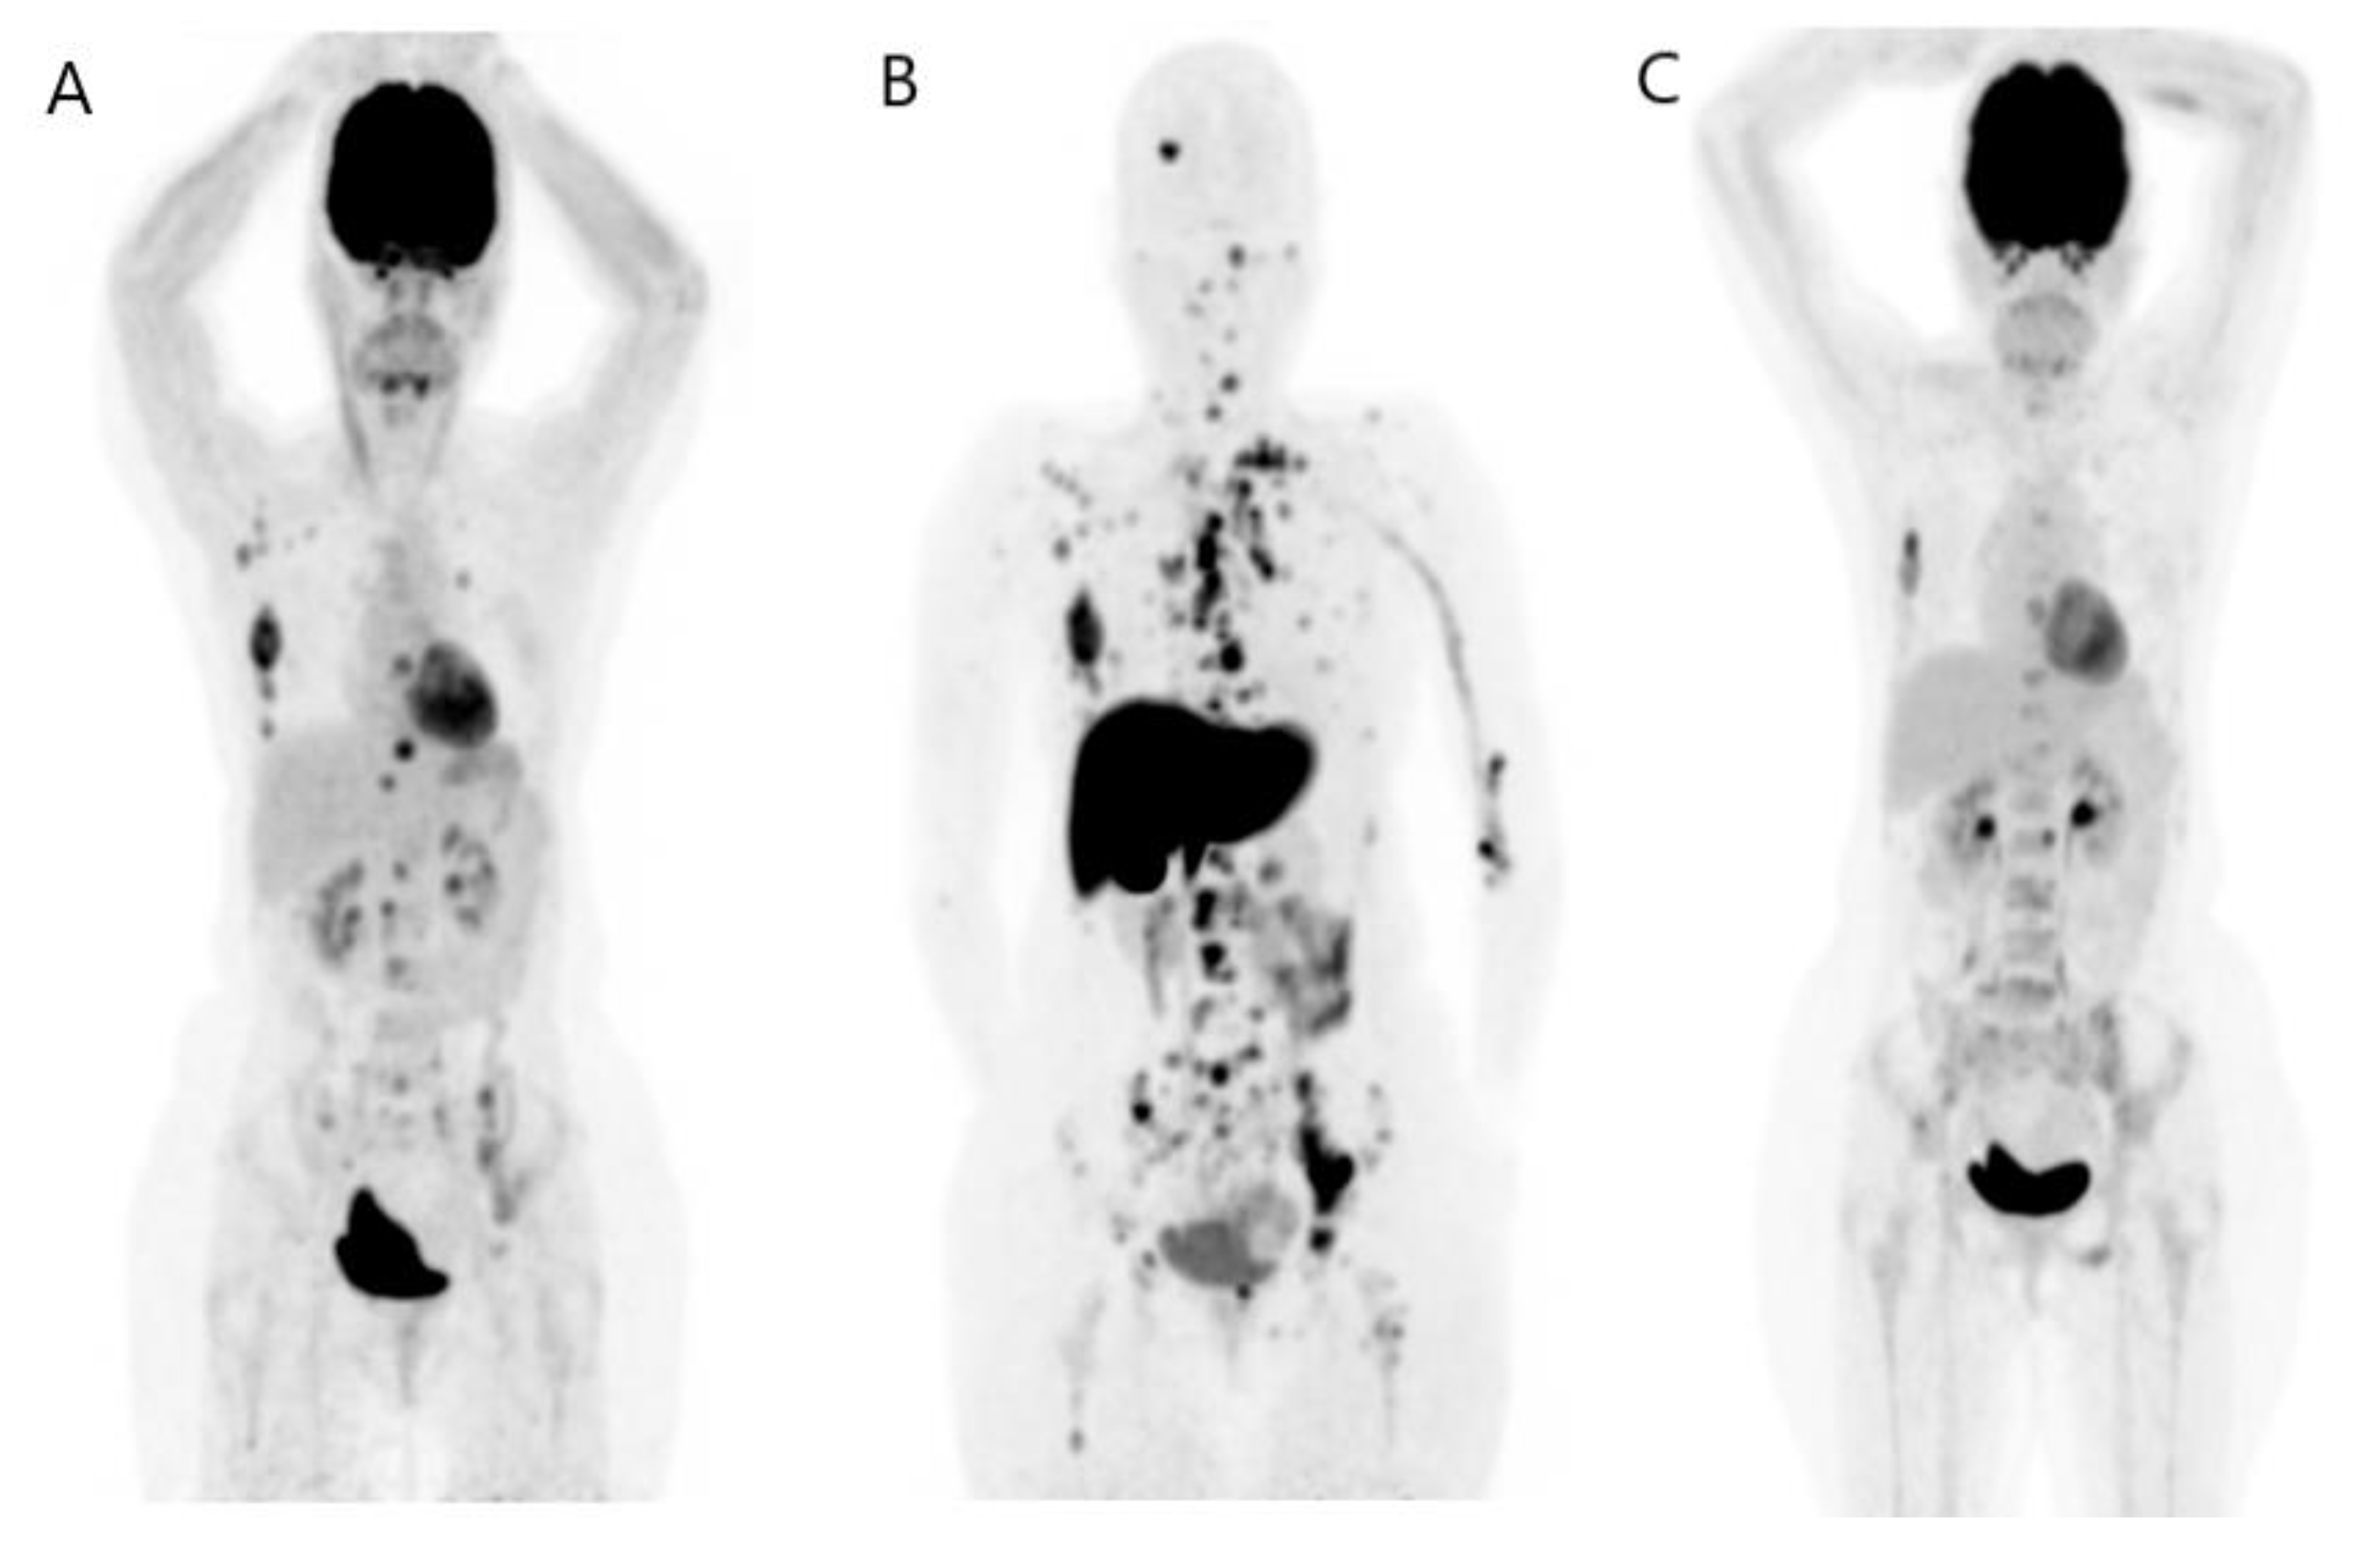

2.3.2. Neoadjuvant Treatment Response for Primary Tumor

- Schwarz-Dose, J.; Untch, M.; Tiling, R.; Sassen, S.; Mahner, S.; Kahlert, S.; Harbeck, N.; Lebeau, A.; Brenner, W.; Schwaiger, M. Monitoring primary systemic therapy of large and locally advanced breast cancer by using sequential positron emission tomography imaging with [18F]fluorodeoxyglucose. J. Clin. Oncol. 2009, 27, 535–541. [Google Scholar] [CrossRef] [PubMed]

- Rousseau, C.; Devillers, A.; Sagan, C.; Ferrer, L.; Bridji, B.; Campion, L.; Ricaud, M.; Bourbouloux, E.; Doutriaux, I.; Clouet, M.; et al. Monitoring of early response to neoadjuvant chemotherapy in stage II and III breast cancer by [18F]fluorodeoxyglucose positron emission tomography. J. Clin. Oncol. 2006, 24, 5366–5372. [Google Scholar] [CrossRef] [PubMed]

- Groheux, D.; Hindié, E.; Giacchetti, S.; Delord, M.; Hamy, A.S.; de Roquancourt, A.; Vercellino, L.; Berenger, N.; Marty, M.; Espié, M.; et al. Triple-negative breast cancer: Early assessment with 18F-FDG PET/CT during neoadjuvant chemotherapy identifies patients who are unlikely to achieve a pathologic complete response and are at a high risk of early relapse. J. Nucl. Med. 2012, 53, 249–254. [Google Scholar] [CrossRef] [PubMed]

- Groheux, D.; Hatt, M.; Hindié, E.; Giacchetti, S.; de Cremoux, P.; Lehmann-Che, J.; Espié, M. Estrogen receptor-positive/human epidermal growth factor receptor 2-negative breast tumors: Early prediction of chemosensitivity with 18F-fluorodeoxyglucose positron emission tomography/computed tomography during neoadjuvant chemotherapy. Cancer 2013, 119, 1960–1968. [Google Scholar] [CrossRef]